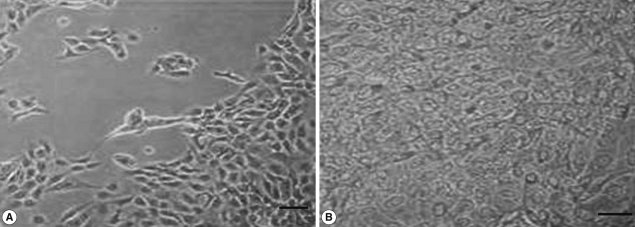

We also analyzed the effects of L. acidophilus on MS74 cells by observing their cellular attachment to the culture plate and counting the number of viable cells. MS74 cells were cultured in T75 cell culture flasks (SPL lifesciences, Pocheon, Korea) in the presence or absence of L. acidophilus. After 24 hr culture, the culture flask was examined under a microscope (×400) (TS100, Nikon, Tokyo, Japan). As shown in Fig. 2, MS74 cells co-cultured with L. acidophilus were more firmly attached to the plate and were more confluent than were those cultured in the absence of L. acidophilus; several detached areas were observed on the latter plate (Fig. 2A). The cells were harvested by incubation with 10% trypsin-EDTA solution (GenDEPOT), and then washed twice and resuspended with PBS via centrifugation at 2,000 g at 4℃ for 30 min. Viable cells were counted by staining the cells with trypan blue followed by visualization under a microscope using a hemocytometer (Superior MarienFeld, Bad Mergentheim, Germany). Differences between groups were analyzed by the Student's t-test using SPSS 17.0 software for Windows (SPSS Inc., Chicago, Illinois, USA). Significance was accepted at P<0.05. More MS74 cells were present in co-cultures with L. acidophilus than in cultures that did not contain L. acidophilus (1.1×107 cells/ml versus 9×106 cells/ml, respectively) (P<0.05) (Fig. 3).